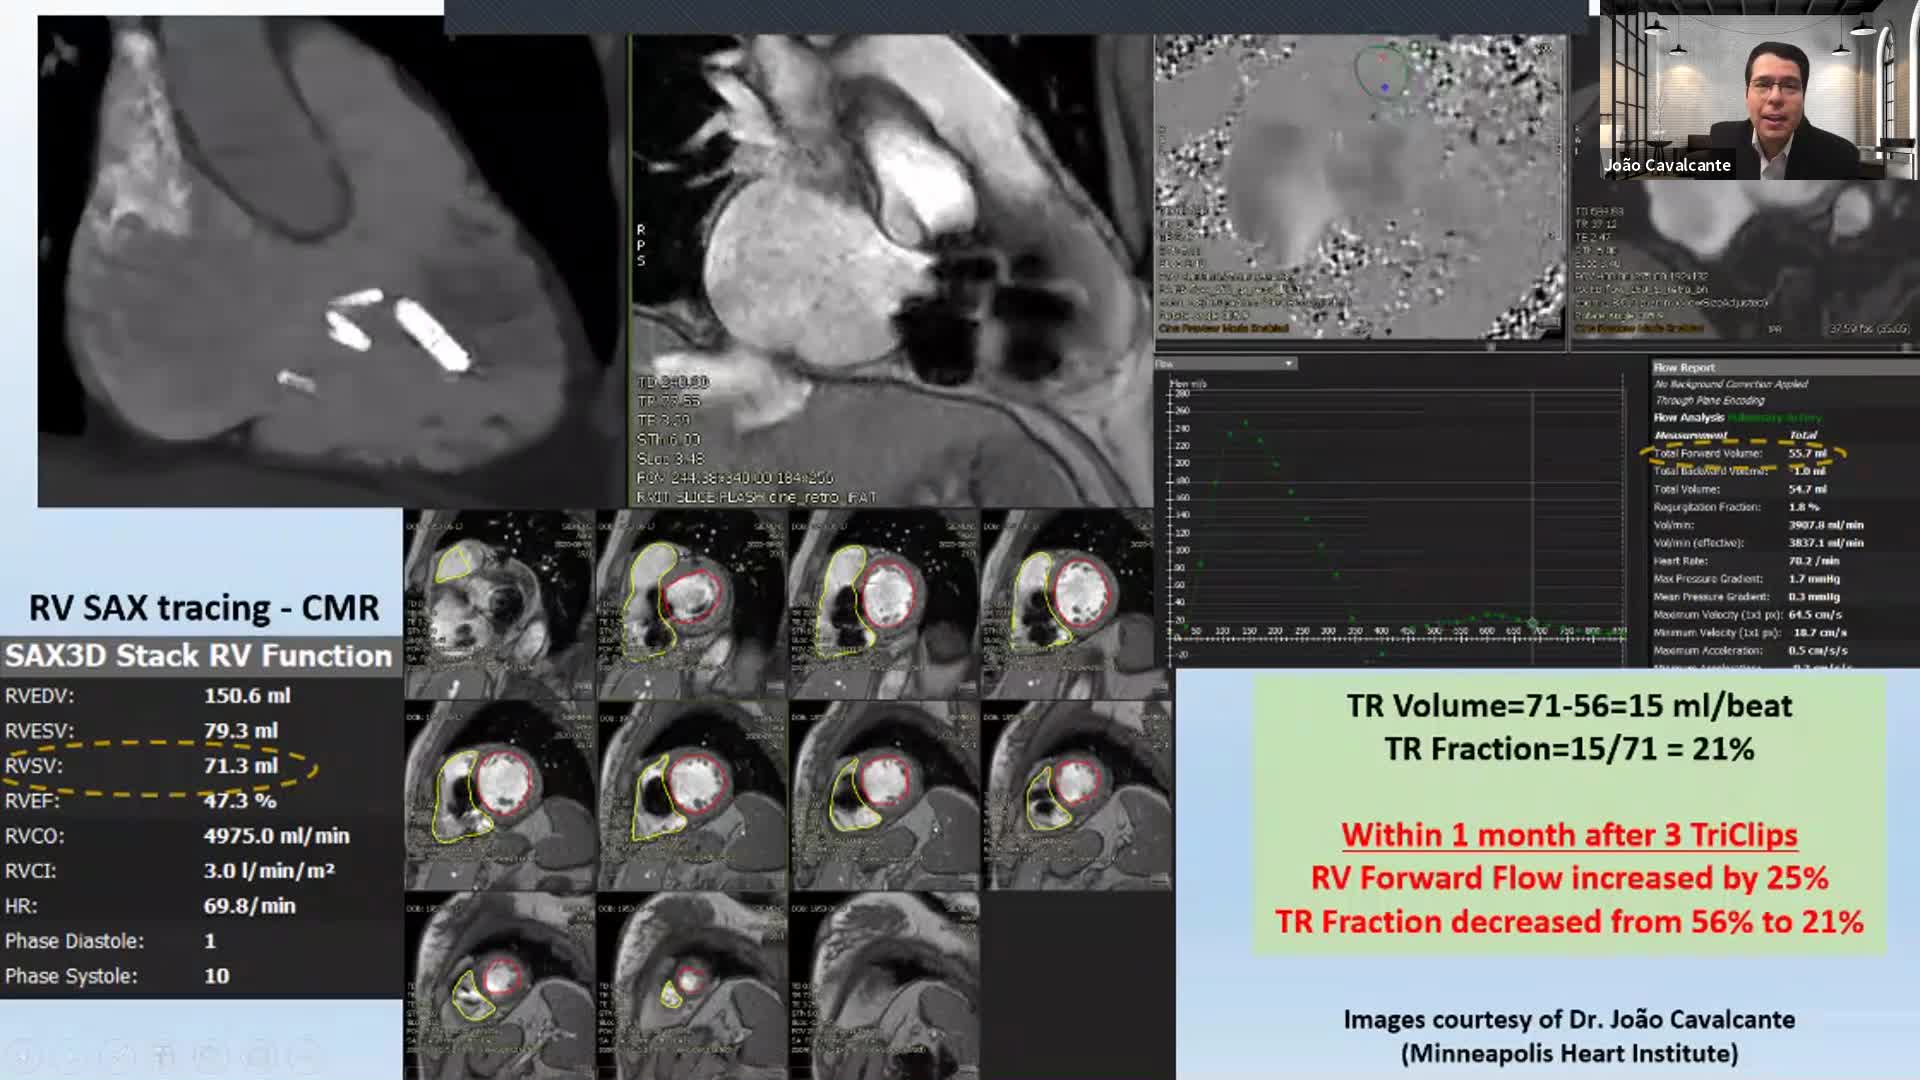

CSI is the leading conference on catheter therapy of congenital, structural and valvar heart disease and heart failure interventions worldwide. Lead by experts in the field, CSI supports and promotes global and multidisciplinary collaboration by providing educational congresses, workshops and online learning opportunities like live cases and webinars. It is our goal to stay at the forefront of technology, innovation and medical device development and we achieve this through close collaboration with our worldwide network of physicians, healthcare providers and industry professionals.